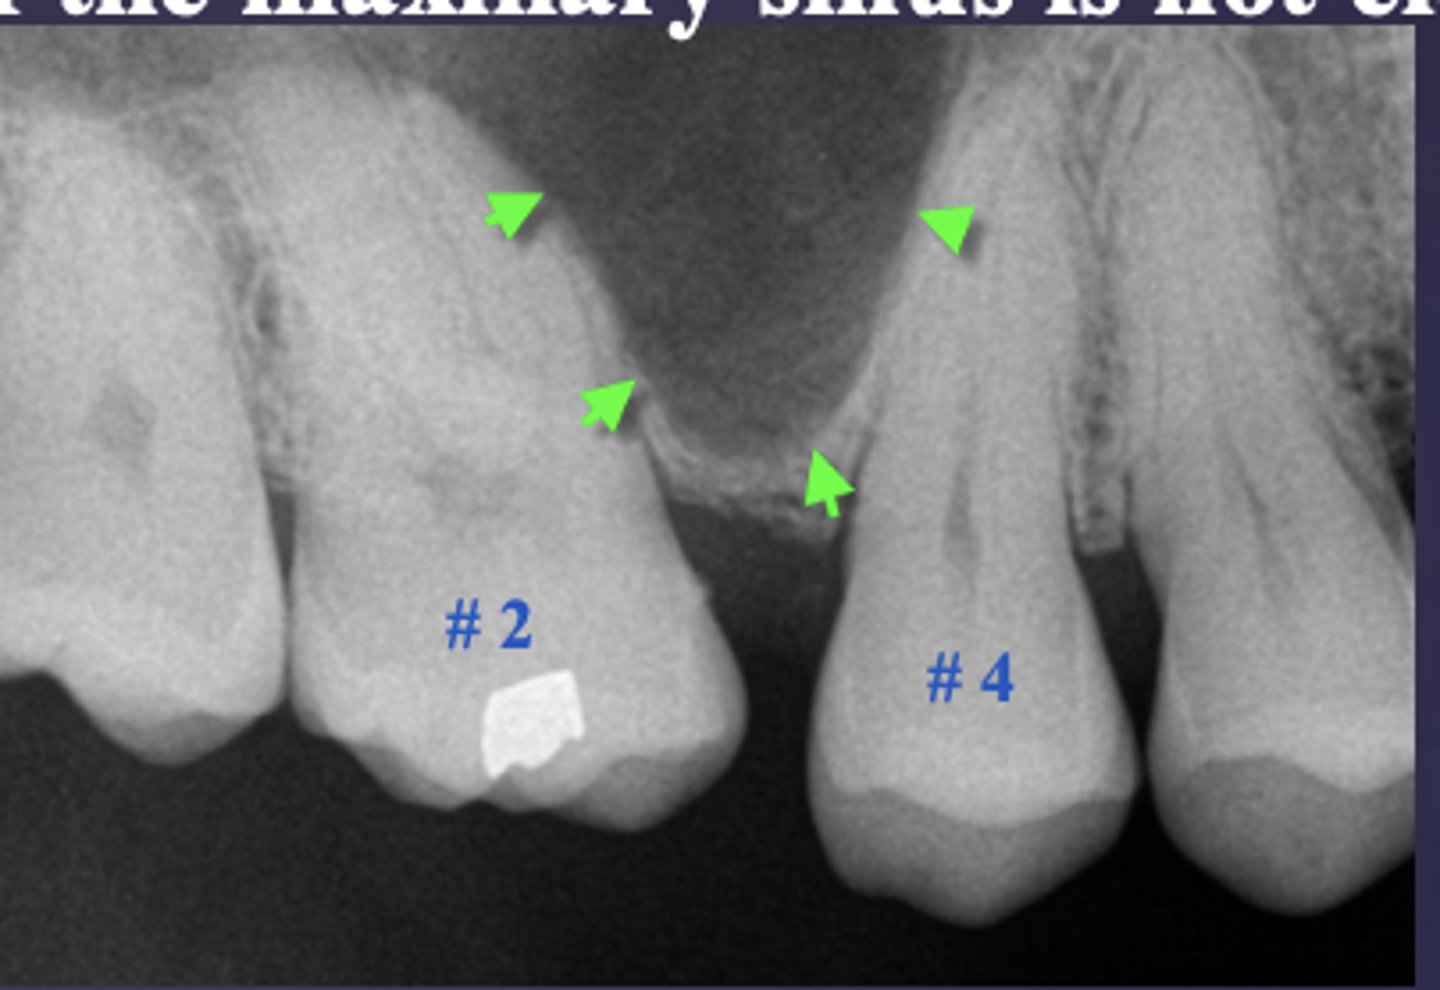

What are the arrows pointing to?

periostitis/onion skin

Periostitis and mucositis

What condition?

maxillary sinus floor periostitis/mucositis